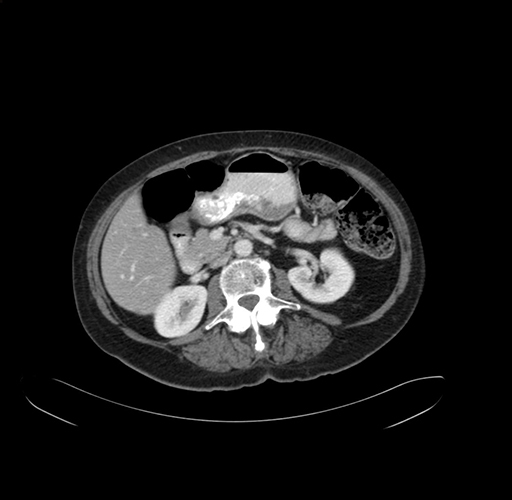

Pre-Chemo: Axial Venous

Axial Venous